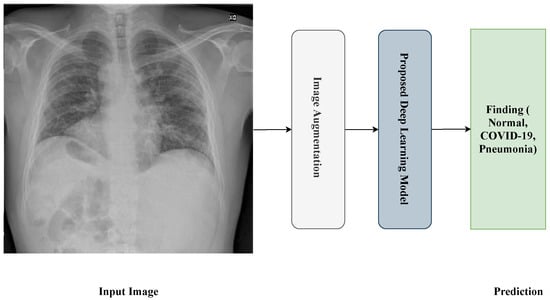

On the other hand, numerous studies have used X-ray images to detect COVID-19, employing various approaches. Prabira et al. [21] proposed a transfer learning technique that consisted of Resnet50 and SVM, to classify COVID-19 using X-ray images. The ResNet50 model was selected after testing eight pre-trained models, including AlexNet, VGG16, VGG19, Google Net, ResNet50, ResNet101, and XceptionNetin order, to use the best. The authors used Resnet50 to extract deep features and then used SVM for classification. Finally, the proposed method was evaluated, using datasets collected from GitHub, Kaggle, and OpenAI. The accuracy achieved was 95.38%. To detect pneumonia using X-ray images, Rajpurkar et al. [5] proposed an algorithm called CheXNet. They trained the dataset on a 121-layer Convolutional Neural Network. The CheXNet dataset, trained on the ChestX-ray14 dataset, contains about 112,120 frontal-view X-ray images with 14 different classes, including pneumonia. Gozes et al. [22] proposed an AI-based tool that uses CT images for Coronavirus detection. This tool combines 2D and 3D deep learning models. They applied segmentation techniques to extract lung regions and then trained six different datasets for patients from China and the U.S. on ResNet50-2D. The sensitivity and specificity achieved were 98.2% and 92%, respectively.

Nahiduzzaman et al. [23] proposed a novel model called the Chest X-ray6 model, which depends on the lightweight CNN model to detect five diseases, including COVID-19. They applied their approach to 9514 Chest X-ray images, which they collected from different databases with six classes. The dataset was unbalanced, they applied five different augmentation techniques, and the number became 21,000 images. Finally, they had two classification tasks: binary and multi-classification. Their model achieved accuracy of 97.94% and 80% for both tasks, respectively. In [24], Constantinou et al. aimed to study the possibilities of a deep learning-based approach to detecting the COVID-19 disease. They focused on five models: ResNet50, ResNet101, DenseNet121, DenseNet 169, and InceptionV3. They evaluated their developed models on the COVID-QU dataset, which contains 33,920 X-ray images in three classes: COVID-19, Non-COVID-19, and Normal. The result showed that ResNet101 outperformed the other models, with accuracy of 96%.

In [25], Dawar et al. developed a system that could distinguish the COVID-19 X-ray disease from others. The dataset used was collected from an open repository that contained 15,000 images categorized into COVID-19, Pneumonia, and Normal. Four Convolutional Neural Network models were used: VGGNet, LeNet5, AlexNet, and their custom model, which consisted of five convolutional layers followed by four dense layers. The result showed that the custom model performed best compared to the other models, with accuracy reaching 93.96%. In [26], Chakraborty et al. proposed a deep learning model dependent on the ResNet18 pre-trained model. First, they collected 10,040 X-ray images from different open sources, like Kaggle and GitHub, to detect COVID-19 images among images classified as pneumonia and normal. Then, they applied their preprocessing steps and fed them into the model. Their model achieved accuracy of 96.43% and sensitivity of 93.68%.

Gupta et al. [27] developed a system dependant on X-ray images to detect COVID-19 diseases. They used an open-source dataset with 2905 images labeled into three classes: COVID-19, viral pneumonia, and healthy. The deep learning models used in this study were VGG16, MobileNetV2, ResNet18, and AlexNet. They concluded that the AlexNet model outperformed the other models, with accuracy of 97.6%. In [28], Dhiman et al. developed 11 Convolutional Neural Network (CNN)-based models—AlexNet, VGG16, VGG19, GoogleNet, ResNet18, ResNet50, ResNet101, InceptionV3, InceptionResNetV2, DenseNet201, and XceptionNet—to detect COVID-19 using X-ray images by classifying them into COVID-19 and normal. The dataset used was collected from open repositories like GitHub and Kaggle. They found that ResNet101 with the J48 decision tree classifier outperformed the other models, with accuracy of 98.54%. In [29], Narin et al. proposed five transfer learning methods based on pre-trained models (ResNet50, ResNet101, ResNet152, InceptionV3, and Inception-ResNetV2). They applied their models on three different binary datasets: 1-(COVID-19 and Normal), 2-(COVID-19 and Viral Pneumonia), and 3-(COVID-19 and Bacterial Pneumonia), using X-ray images. They concluded that the ResNet50 model achieved the best results among the models on the three datasets, with accuracy for dataset 1: 96.1%, dataset 2: 99.5%, and dataset 3: 99.7%, respectively. In [30], Ozturk et al. proposed a deep learning model based on the Darknet-19 model, with some modifications to the number of filters and convolutional layers, named the DarkCovidNet model. Their study was based on X-ray images collected from two different resources with three classes. They conducted their study on two classification tasks: binary (COVID and no-findings) and multi-classification (COVID, no-findings, and pneumonia). Their model achieved accuracy of 98.08% and 87.02% for both tasks, respectively. Enas in [31] utilized a deep learning framework for early COVID-19 diagnosis using Chest X-ray images, with preprocessing for image enhancement and a classification phase applying pre-trained Convolutional Neural Network models (VGG19 and EfficientNetB0). The best model achieved high sensitivity of 0.96, specificity of 0.94, precision of 0.9412, an F1 score of 0.9505, and accuracy of 0.95 for binary classification of COVID-19 and normal Chest X-rays, and classification accuracy of 0.935 for a four-class classification. Recently, [32] explored the effectiveness of several deep learning models, including Xception, VGG-16, and ResNet. Their work utilized two datasets: the first comprised 4050 X-ray images, and the second had 6378 images. Their results demonstrated that the Xception-Enhanced Model achieved precision of 98.8%, significantly outperforming the ResNet50 model, which had precision of 60%. The standard Xception model and VGG-16 also performed well, with precisions of 86.74% and 92%, respectively.

Recently, several studies in the detection of COVID-19 from Chest X-rays have been introduced, utilizing different deep learning models. Bukhari et al. [33] utilized DenseNet169, demonstrating validation accuracy of 100%, outperforming the ResNet and VGG models. Roy et al. [34] proposed a model combining Xception, InceptionV3, and ResNext50, resulting in accuracy of 98.44%, which showed a 4.44% improvement over prior studies. Comparing the proposed model in this work, the utilization of Xception for both binary and multi-class classification achieved similar binary classification accuracy of 98.13% and multi-class accuracy of 87.73%. The results obtained in our research illustrate the proposed approach’s competitiveness with other state-of-the-art models, especially for multi-class classification tasks, where our model performed comparably to more complex architectures. Moreover, Ramkumar et al. [35] have proposed a new approach that combines MobileNetv1 with Jellyfish Search Optimization for COVID-19 detection. The proposed method includes multi-head attention mechanisms that improve precision and computational efficiency. However, our proposed model maintains high accuracy and recall without requiring additional optimization techniques, which reinforces the model’s simplicity and robustness. Henna et al. [36] also used transfer learning techniques, with CLAHE-based data augmentation, to train models like AlexNet and VGG16 on smaller datasets. Our proposed Xception-based model with extensive data augmentation achieved superior results on a much larger dataset, which shows the scalability and efficacy of our proposed approach. More recent proposed models, such as Singh et al. [37], used VGG16 with transfer learning for COVID-19 detection, showing strong results in feature extraction using data augmentation and pre-trained weights. Ali et al. [38] utilized a modified CNN with k-Nearest Neighbor to classify COVID-19 severity, reporting 92.80% testing accuracy. Meanwhile, Rashed et al. [39] utilized a Conditional Cascaded Network (CCN) with transfer learning, showing high precision and specificity using multiple datasets, while Khattab et al. [40] integrated focal loss with several deep learning models, like InceptionResNet V2 and Xception, and they showed classification accuracy of up to 100% on some datasets. While these proposed works emphasized the adaptability of transfer learning and optimization techniques, our proposed model combines Xception and data augmentation, yielding 87.73% multi-class accuracy and 90.20% precision, thus remaining highly competitive in both performance and simplicity. Additionally, the work proposed by Rashed et al. [39] employed a CNN approach for COVID-19 diagnosis using Chest X-rays and CT images, demonstrating robust performance metrics across different architectures. Moreover, the work of Khattab et al. [40] combined transfer learning models and data-mining techniques for class imbalance. These comparative results indicate that while several state-of-the-art techniques utilize complex multi-model architectures or novel optimization methods our proposed approach remains competitive, with a focus on simplicity, transfer learning, and effective data augmentation.